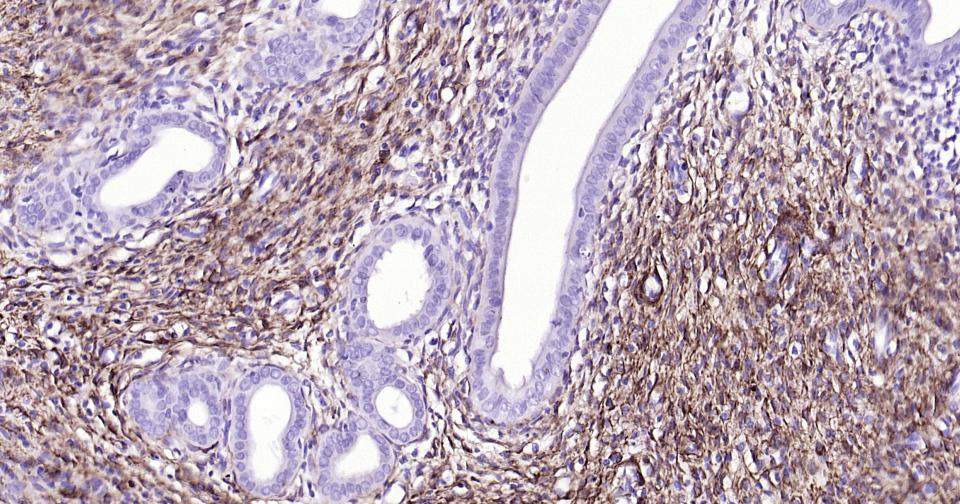

IHC-PHuman, Mouse, Rat1:100-500

IHC-FHuman, Mouse, Rat1:100-500

IFHuman, Mouse, Rat1:100-500

ICC/IFRatHuman, Mouse1:50-200